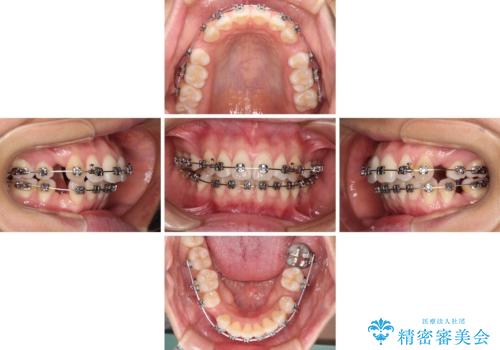

- 矯正装置

- メタルブラケット

- 治療期間

- 1年11ヶ月

非抜歯矯正ではデコボコを解消することでより口元が突出してしまうため、上下左右の小臼歯4本の抜歯を行い、ワイヤー装置による矯正治療を行うこととしました。